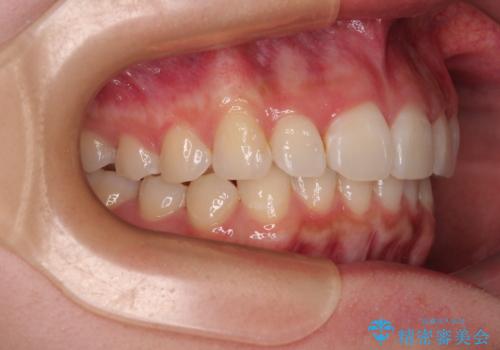

- 前歯のデコボコと突出感を気にして来院された患者様です。

極力目立たない装置を希望とのことで、インビザラインを用いて非抜歯で矯正治療を行うこととしました。

事前に親知らず2本を抜歯し、多少歯列を後方に移動できるように準備をした上で、なるべく歯と歯の間を削ることなくデコボコを解消できるように計画しました。

前歯の捻れを改善するとともに、口元が少しでも引っ込むように治療計画を立て、仕上げることができました。